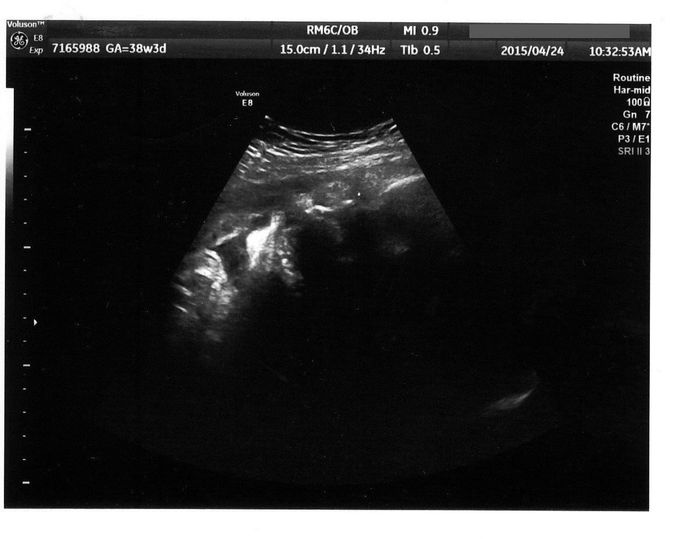

出産直前! - 妊娠38週目のエコー写真

出産前日のエコーです。真ん中の薄い線が背骨、上のところが腰だと思います。この頃は、赤ちゃんの頭は私の骨盤の方にあり、顔を見ることはできませんでした。

赤ちゃんの体重がまったく増えなくなり、37週で管理入院することになりました。赤ちゃんの推定体重は2000g程度で、誤差を含めると2000g以下の可能性もあり、低体重児になってしまいます。ちょうどよく大型連休に入り、夫が家で上の2人の子どもの面倒を見ることに。病院の食事は薄味だけどおいしくて、カロリー計算も完璧。赤ちゃんの体重を増やそうとたくさん食べていた私ですが、入院中に2kgやせてしまいました。